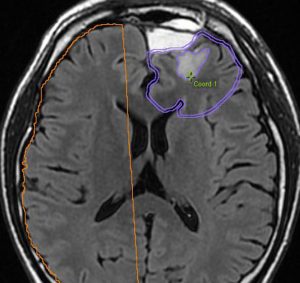

40代の患者さんです。夜間睡眠中の全般発作(症候性てんかん)で発症しました。フレア画像で左上前頭回に滲むような高信号領域(白い部分)がみられます。右側はガドリニウム増強MRIですが,全く増強されません。グレード2か3の星細胞腫あるいは乏突起膠腫を疑います。白く滲むような領域はよく見るとかなり広範囲に広がっています。

画像上では全摘出 gross total removalできて,病理診断は,退形成性乏突起星細胞腫 anaplastic oligoastrocytomaでした。IDH変異あり,1p/19q欠失なしです。現在の診断なら,退形成性星細胞腫 グレード3です。

手術後に54グレイの広範囲な局所放射線治療とテモゾロマイド化学療法を行いました。左の画像は放射線治療計画の時の線量分布図です。

5年後にいきなり激しい再発を生じました。再発部位は,放射線照射野外 out-of-fieldの前頭部帯状回でした。手術前に急速に増大して,画像所見も初回と全く違いました。摘出後の病理は,IDH1/2 wild type, 1p/19q intact, ATRX negative, MGMT met negative, MIB-1 40%という典型的な膠芽腫の所見でした。

この例とは異なって,退形成性星細胞腫の再発時には,IDH mutantのままの方が多いです。もしかすると先行した放射線誘発膠芽腫かもしれません。